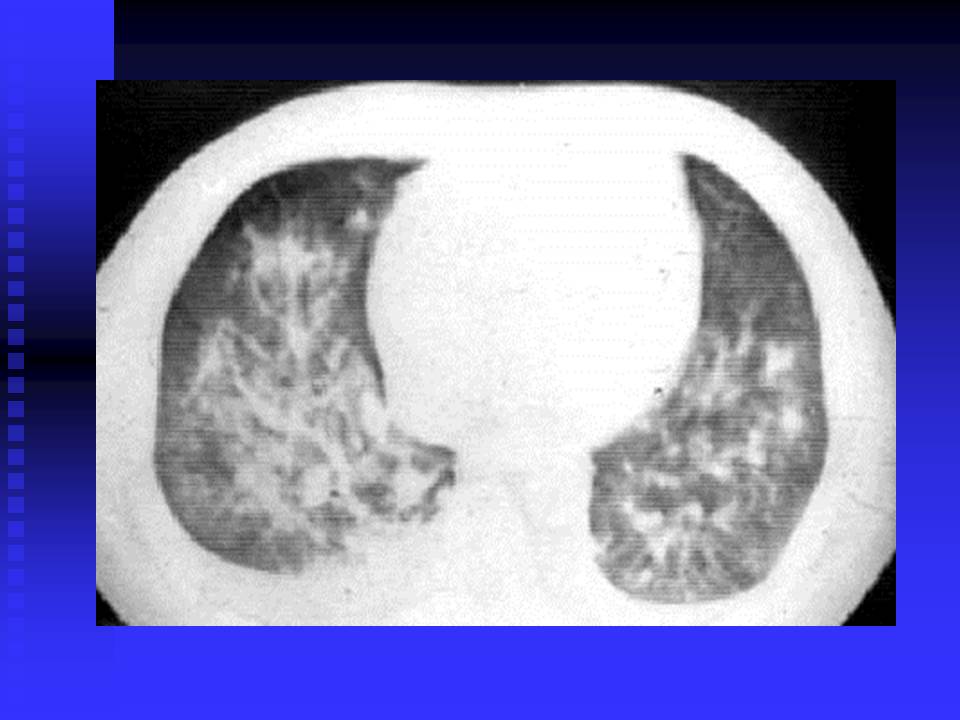

【PPT】严重急性呼吸综合征的影像鉴别诊断